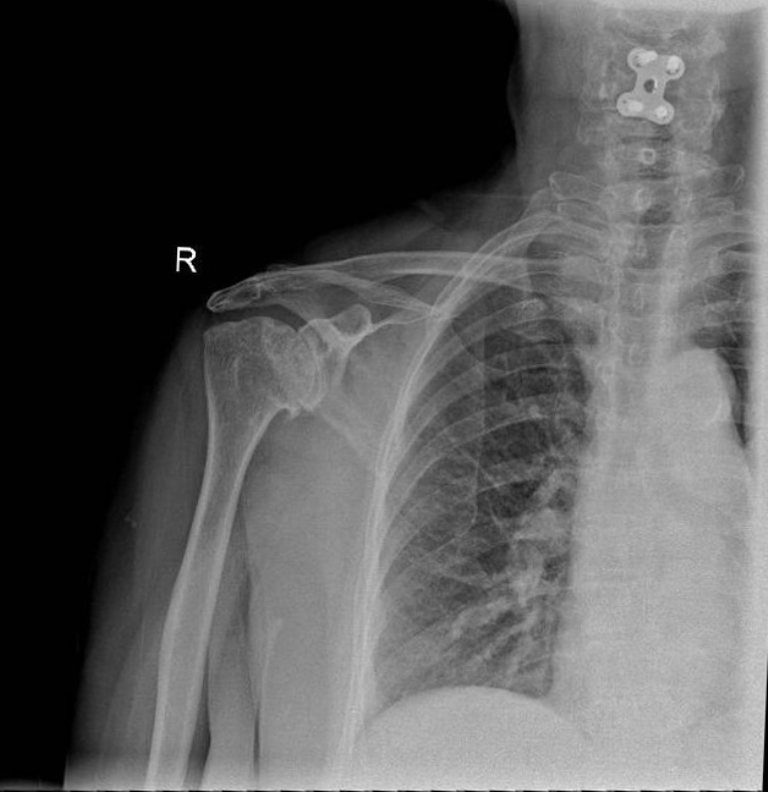

Hình chụp X-quang trước phẫu thuật cho thấy khe khớp vai của người bệnh bị hẹp do lớp sụn bị mài mòn,gai xương hình thành ở rìa mặt khớp, xơ xương dưới sụn.

Tại phiên đào tạo về “Phẫu thuật chấn thương khớp vai”, các bác sĩ khoa Chấn thương chỉnh hình BV ĐHYD TPHCM sẽ tiến hành đào tạo và mổ thị phạm, truyền hình trực tiếp kỹ thuật thay khớp vai nghịch đảo toàn phần tới đại biểu tham dự tại Hội trường 3A. Phẫu thuật được thực hiện trên người bệnh T.H., 73 tuổi, ngụ tại TPHCM. Bà H. nhập viện trong tình trạng đau và mất chức năng khớp vai phải. 2 năm nay, bà H. không thể dùng tay phải trong sinh hoạt hằng ngày như chải tóc, mặc áo… Sau khi thăm khám, chụp X-quang và MRI, các bác sĩ chẩn đoán bà bị thoái hóa khớp vai bên phải mức độ nặng do biến chứng của viêm khớp dạng thấp. Bà được chỉ định phẫu thuật thay khớp vai nghịch đảo toàn phần. Các bác sĩ cho biết, việc áp dụng phẫu thuật này giúp người bệnh giảm đau, phục hồi chức năng khớp vai để người bệnh có thể trở lại vận động, sinh hoạt bình thường như trước.